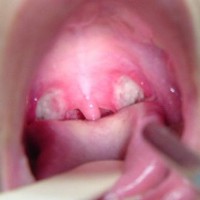

ontstoken keelamandel

Artikel: Ontstoken Keelamandel Ontstoken Keelamandel: Symptomen, Oorzaken en Behandeling Een ontstoken keelamandel, ook wel bekend als tonsillitis, is een veelvoorkomende aandoening die ongemak en pijn in de keel veroorzaakt. De keelamandelen zijn twee amandelvormige weefsels aan weerszijden van de achterkant van de keel en spelen een rol bij het bestrijden van infecties. Wanneer deze amandelen […]

Artikel: Ontstoken Amandelen Ontstoken Amandelen: Symptomen, Oorzaken en Behandeling Ontstoken amandelen, ook wel bekend als tonsillitis, is een veelvoorkomende aandoening die zowel bij kinderen als volwassenen kan voorkomen. De amandelen zijn twee kleine klieren aan de achterkant van de keel die een belangrijke rol spelen bij het bestrijden van infecties. Wanneer deze klieren geïnfecteerd raken, […]